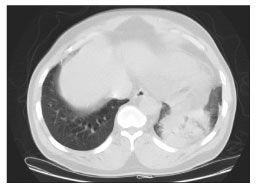

On arrival to the emergency department, S.M. was febrile (temperature, 39.7°C [103.5°F]). He was hemodynamically stable with a room air oxygen saturation of 96%. The physical examination revealed basilar rales on the left with bronchial breath sounds and egophony. The results of the initial laboratory tests included an elevated white blood cell count (14.1 × 109/L, with 86% neutrophils), and hyponatremia (sodium level of 130 mmol/L [normal, 133 - 147]). Results of liver function tests were normal. Chest radiographs and CT scans confirmed a left lower lobe consolidation (Figures 1 and 2). Therapy with piperacillin/tazobactam was started for presumed bacterial pneumonia, and the patient underwent fiberoptic bronchoscopy.

Figure 2.A CT scan of the chest showing left lower lobe consolidation with air bronchograms. (Image courtesy of the department of radiology, New York-Presbyterian Hospital-Weill Medical College of Cornell University.)